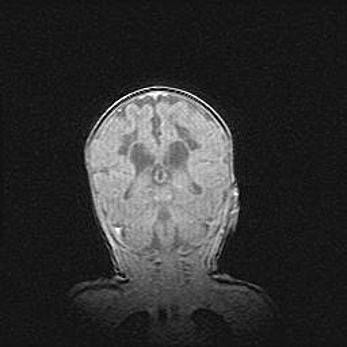

Множественные кисты обоих полушарий головного мозга, наибольшая из них в правой затылочной области. Ассиметричная атрофическая гидроцефалия.

Возраст: 7 месяцев

Вес: 5660 г

Пол: мужской

Окружность головы: 41,5 см

Срок гестации: 28-29 недель

Кисты головного мозга развиваются в результате многоочаговых некрозов вещества мозга и возникают вследствие перенесенной перинатальной инфекции, менингитов, энцефалитов, асфиксии, родовой травмы, расстройств мозгового кровообращения различного генеза. Образованию кист в веществе головного мозга плодов и новорожденных способствуют такие факторы, как высокое содержание в нем воды, недостаточная (или отсутствие) миелинизация и слабая астроглиальная реакция на повреждение.

Кисты могут сочетаться с гидроцефалией и другими поражениями головного мозга.